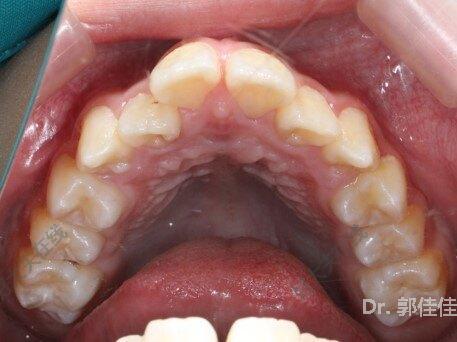

治疗前

11岁小男孩,主诉龅牙,牙齿不整齐。

检查:侧貌突,开唇露齿。上颌前突,下颌后缩,上前牙前突10mm左右,咬合深,咬至上颌粘膜,上下牙弓狭窄,牙列拥挤不齐。